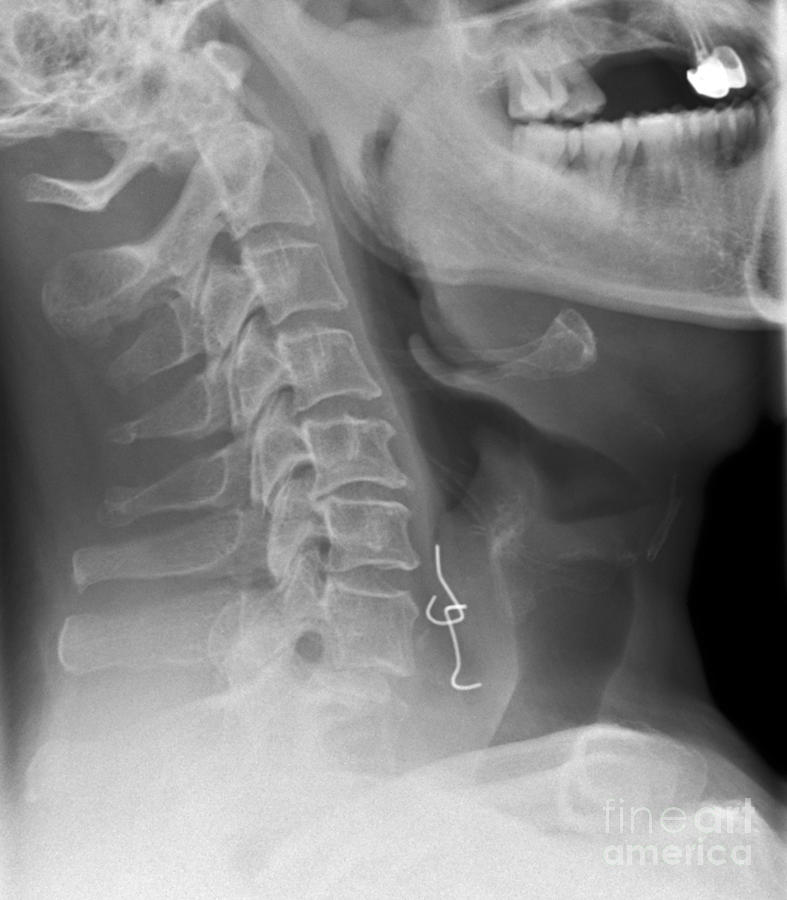

From fineartamerica.com

Swallowed Denture, Xray Photograph by Du Cane Medical Imaging Ltd. How To Remove Swallowed Denture What should you do now? fish bones, followed by other types of bones, followed by dentures, are what most often end up in adults' digestive tracts,. Fixed dentures are also at. A tooth, dental restoration, or bracket from your braces just fell out — and you swallowed it. if they were teeth that were part of a dental. How To Remove Swallowed Denture.